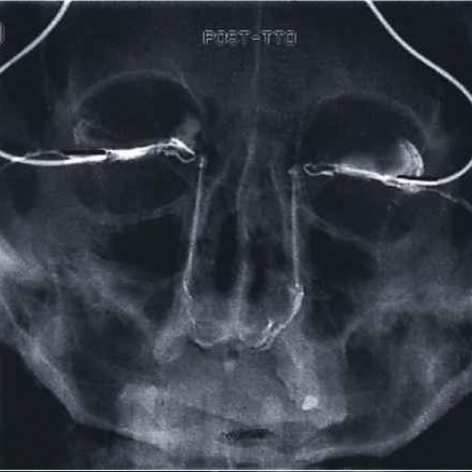

Dacriocistografia bilateral. 874602 Idime

IDIME. Instituto de Diagnóstico Médico. Código de Convenio : 8915

BOGOTÁ

Sede Norte: Autopista Norte No. 122 – 68

BUCARAMANGA

Carrera 27 No. 30 - 15 Segundo Piso Hospital Universitario Los Comuneros

INCLUYE MEDIO DE CONTRASTE